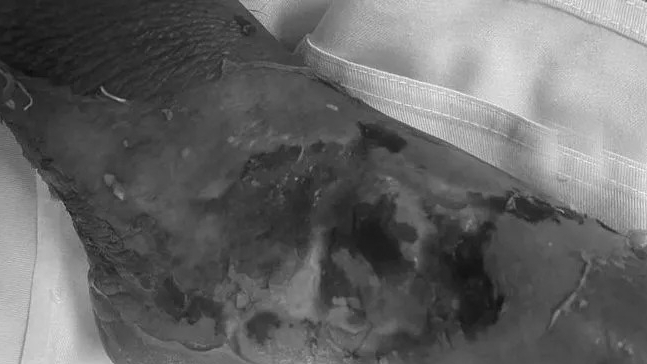

Anh Nguyễn Văn T (34 tuổi), trú tại Đội Cấn, huyện Yên Sơn, nhập viện ngày 15/9 trong tình trạng cẳng chân 2 bên sưng tấy, phỏng nước, có phần trợt da, có phần hoạt tử đen kèm theo chảy mủ hôi…được chẩn đoán bỏng độ II, III (diện tích khoảng 16%), một số vị trí bỏng độ IV (diện tích 3%).

Gia đình bệnh nhân T cho biết: Trước khi nhập viện 4 ngày, khi bệnh nhân đang sử dụng bếp ga công nghiệp, bất ngờ dây ga tuột bắn ra khỏi bếp, bén lửa và gây bỏng nặng cho bệnh nhân T. Sau bỏng, gia đình đã nghe người quen giới thiệu lấy “thuốc nam” của 1 “bà lang” về để đắp, nhưng không đỡ, càng ngày càng sưng to và đau rát, nên gia đình đã đưa bệnh nhân T đến Bệnh viện đa khoa tỉnh Tuyên Quang khám bệnh và điều trị.

Bác sỹ Chuyên khoa II Ngọc Đại Cương, Phó Giám đốc Bệnh viện kiêm Trưởng khoa Chấn thương Chỉnh hình, Bệnh viện đa khoa tỉnh Tuyên Quang cho biết, thời gian qua, Bệnh viện đã tiếp nhận rất nhiều trường hợp nhập viện điều trị trong tình trạng nhiễm trùng vết bỏng do đắp thuốc nam không rõ nguồn gốc. Có những bệnh nhân vùng bỏng đã hoại tử sâu, phải ghép da rất phức tạp, thời gian điều trị kéo dài và tốn rất nhiều chi phí.